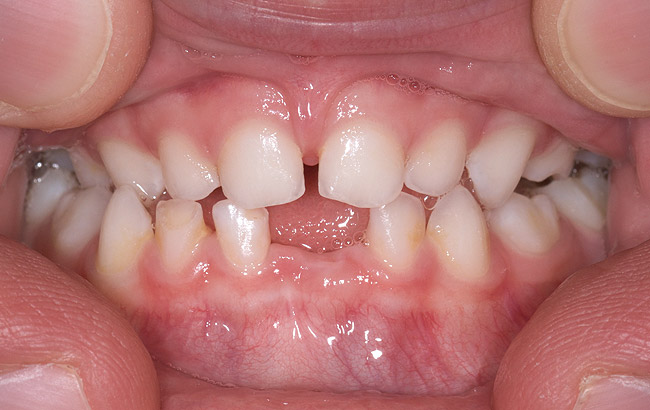

(3.) Three-year-old with a history of snoring, bruxing, and thumbsucking. Her father and brother were both diagnosed with OSA.

Figure 3

(4.) Patient presents bilateral crossbite and significant attrition. Father assists in retraction.

Figure 4